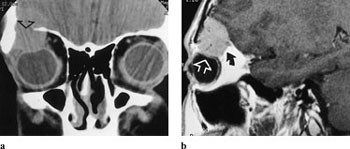

Dermoid- og epidermoidcyster vokser langsomt og eroderer orbitalt bein. Karakteristisk lokalisasjon er i den superolaterale og superomediale delen av orbita, og sees som en diskret, cysteliknende struktur med en tetthet på CT svarende til væske eller fett. Spesielt viktig er det å fremstille orbitataket, for å utelukke intrakranial utbredelse.

Lymfomer involverer oftest øvre del av orbita, inklusive øvre rette øyemuskel, og presser øyet nedover (fig 8 a, b). Det er svært vanskelig å differensiere røntgenologisk mellom lymfoid lesjon og lymfom i orbita, men der er også overlapping mellom de forskjellige typer histologisk. Karakteristisk er det, som også ved myositt, at muskelsenen er affisert. Både på MR og CT sees lymfomene som homogene, velavgrensede strukturer.